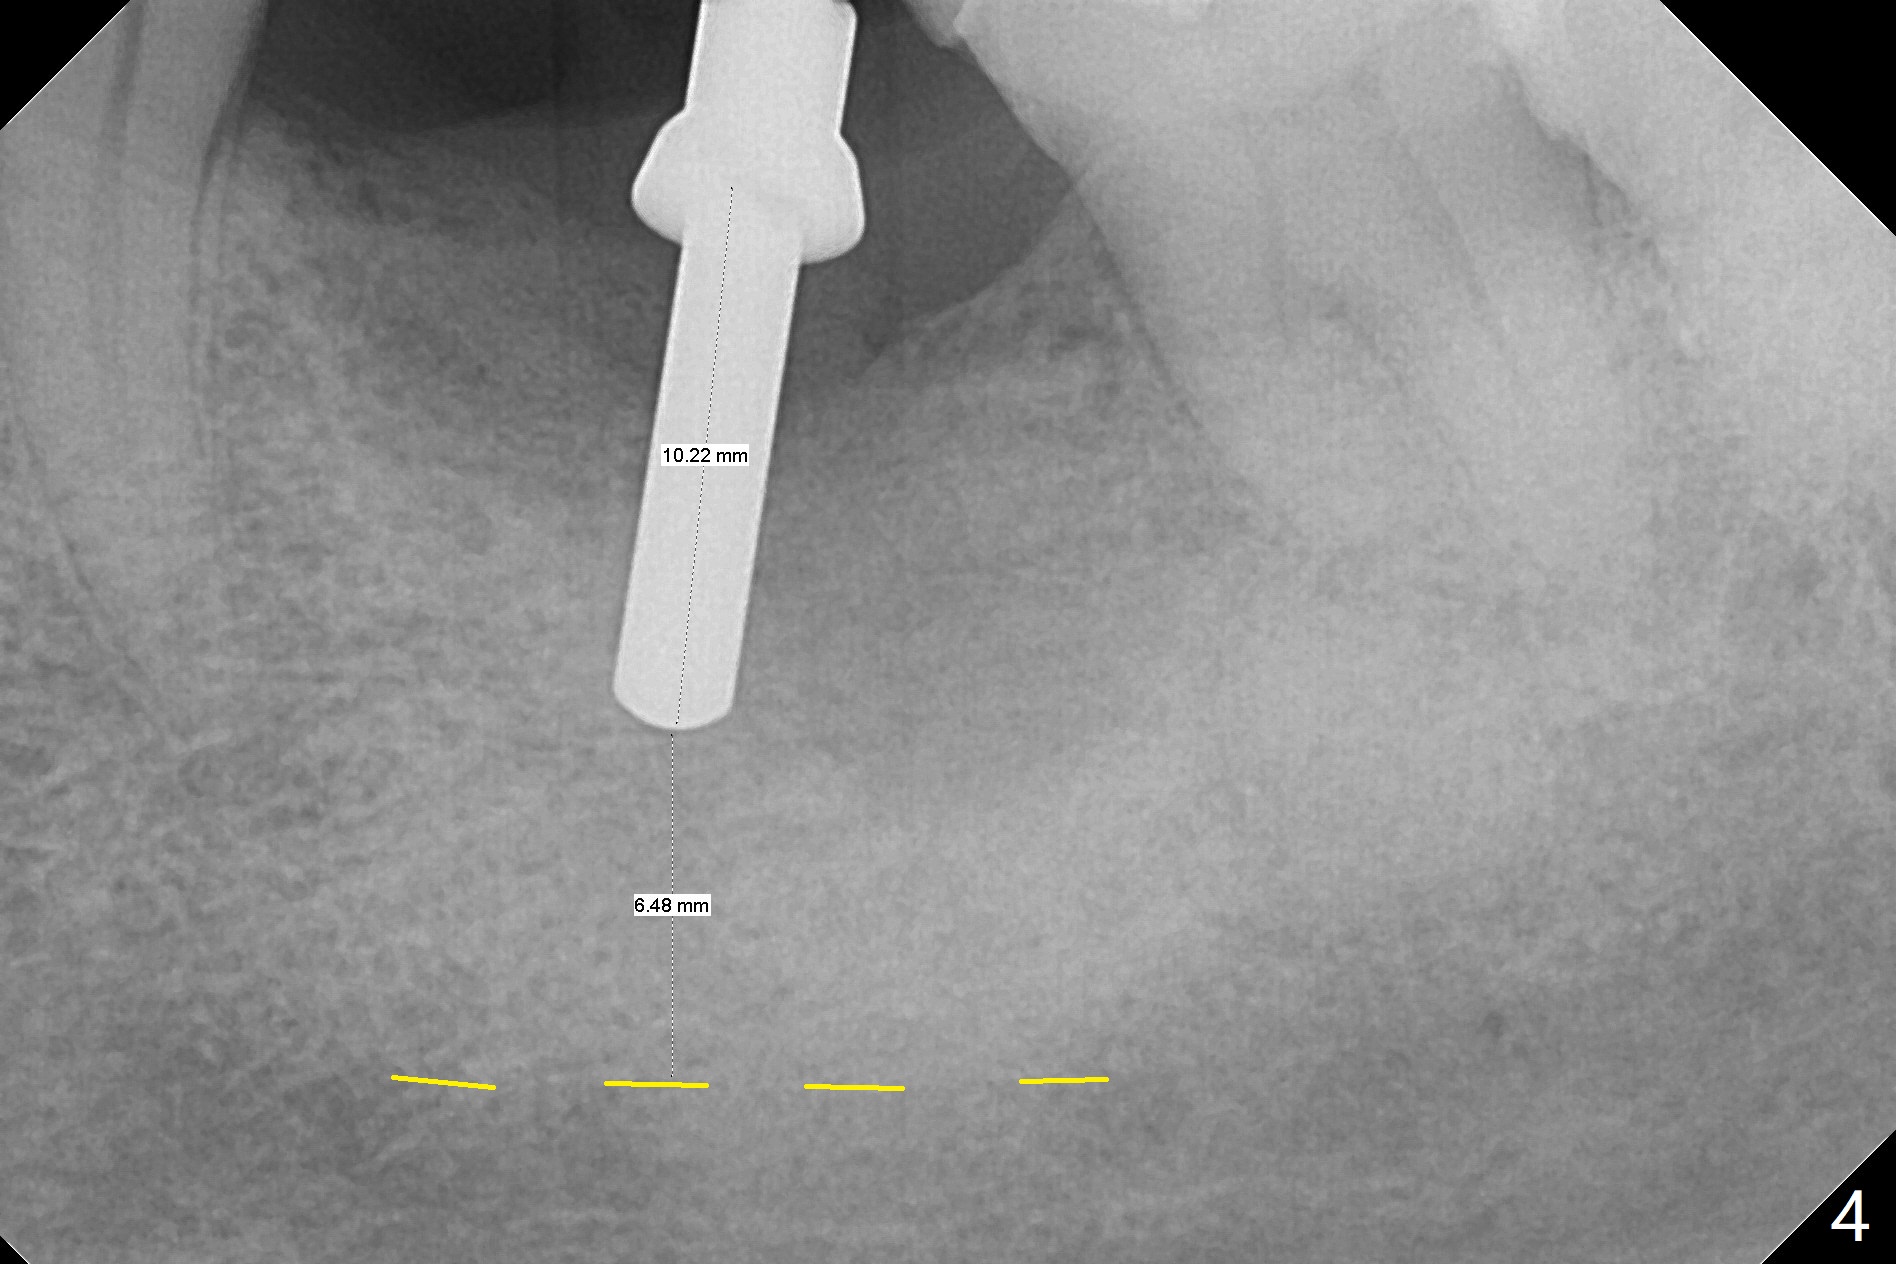

CT taken 4-5 months post extraction shows the outline of the socket at #19 (Fig.1 pink and red dashed line). By the time of surgery (6-7 months post extraction), the ridge looks narrow (Fig.2). In fact the socket does not heal (Fig.3). Osteotomy starts at the mesial border of the socket (Fig.4). When a 5x10 mm dummy implant is placed, the axis begins to be tilted distally (Fig.5 red line), which is more obvious when a definitive longer implant (5x11.5 mm) is placed (Fig.6,7). Osteotomy (Fig.1 arrow) at the mesial slope of the socket (red dashed line) should be initiated more mesial to compensate for the distal drifting while osteotomy is being increased and the implant is being placed. The distal defect is filled with Vanilla graft. Probably due to the mesial slope and the distal defect, the primary stability is <10 Ncm. A healing screw is placed with Vanilla allograft/autogenous bone. The bone forms coronal to the implant 4 months postop (Fig.8 *), which is removed for uncover. The mesial gingival embrasure of the permanent crown is large (Fig.9 *), as related to the mesial undercut associated with a 5.7x4 mm A 15 degree angled abutment (Fig.10). Reduction in the undercut should be able to help lab decrease the gingival embrasure (Fig.11 red line). The bone density around the implant increases with distinct trabecular pattern consistent with stress 5 months post cementation (1 year postop, Fig.12).